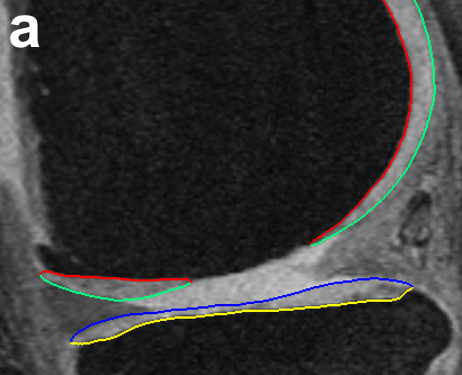

The first step in the sub-plate extraction is the detection of the trochlear notch. The notch is at the base of a groove along which the patella (knee cap) slides over the femur (Fig. 10). The main anatomic feature exploited is anterior to posterior (AP) curvature of the groove of the femoral bone (Fig. 10b). The notch is at the base of the curvature before the bone ridge rises sharply. An implicit cutting plane was used to isolate the analysis region represented by where is the normal direction from the plane and is a point on the plane. When isolating the groove regions using simple implicit plane cutting, a family of contours were drawn along this surface. The sharp rise of the bone structure along the contour near the base of the ridge gives a large change in contour positioning value traversing in the AP direction. To increase robustness we find the positions of largest change on all of the closely positioned groove contour lines and average them to find the desired trochlear notch (Fig. 11).

B-B Sub-Plate Detection using Implicit Cutting Plane Geometry

Using implicit cutting planes at the trochlear notch separates the posterior region from the anterior and further splits them into the medial and lateral condyle. For each femoral condyle, the load-bearing regions is defined as 60% of the distance in the AP direction from the trochlear notch to the posterior-most point of the respective condyles. Isolating them using cutting planes normal to the AP plane at the 60% region isolates the load-bearing regions of the central medial and lateral femur (Fig. 11b).